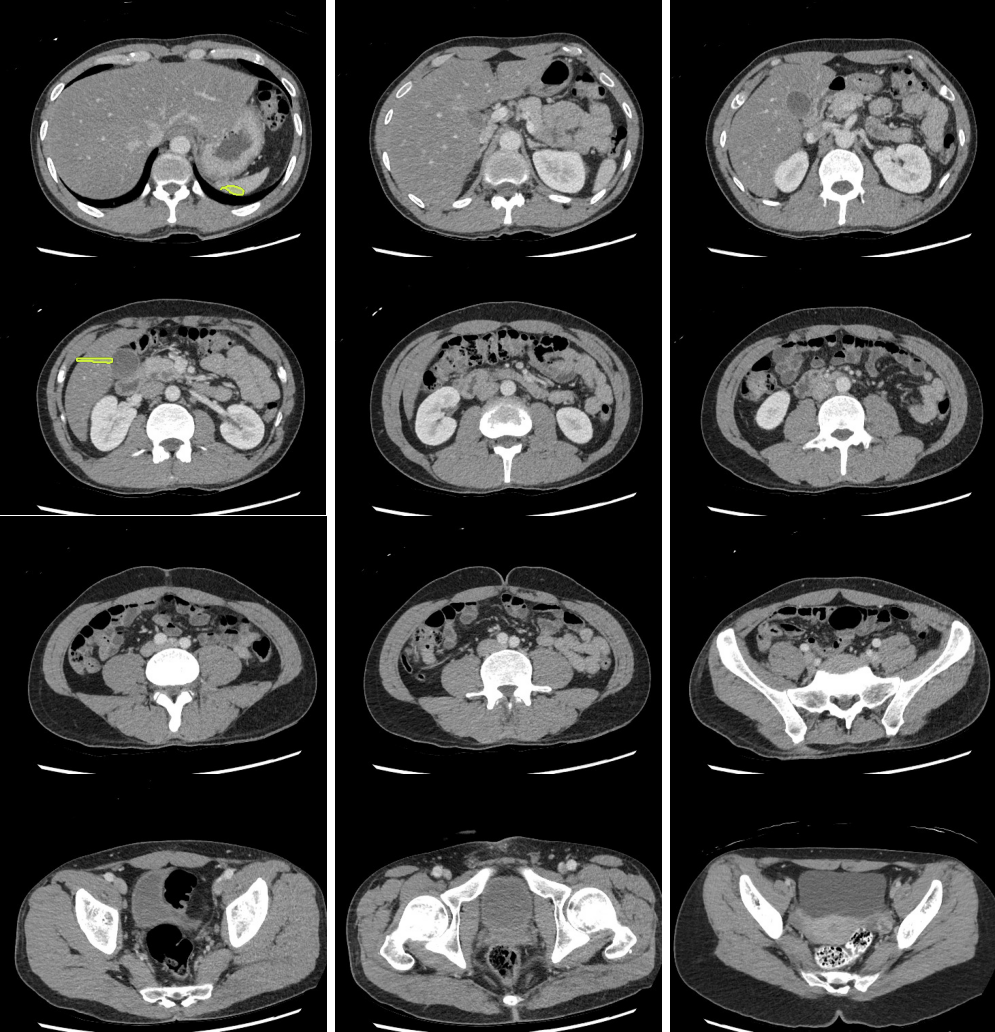

Legend

Slice 1

Slice 2

Slice 3

Slice 4

Slice 5

Slice 6

Slice 7

Slice 8

Slice 9

Slice 10

Slice 11

Slice 12